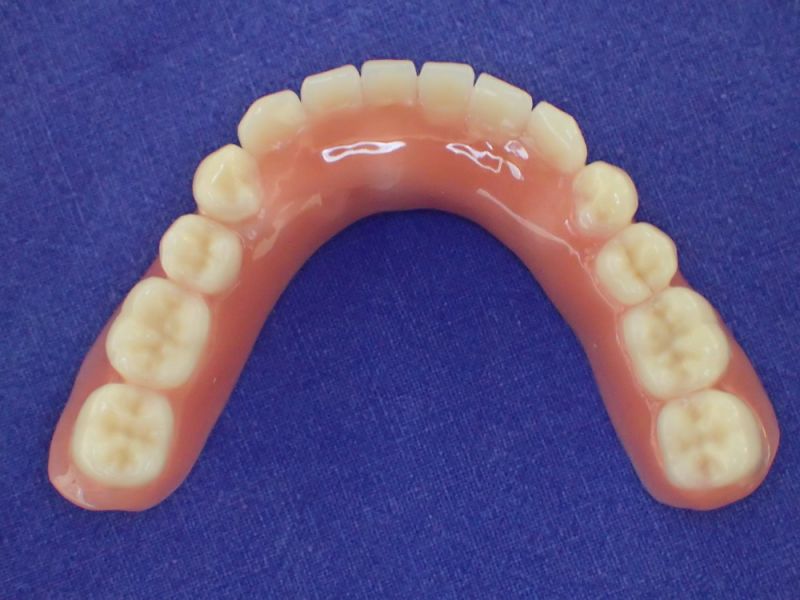

Nach inzwischen 12 jähriger Tragedauer wurden alle Kunststoffteile erneuert, das metallische Grundgeroüst der Arbeit erhalten und die Arbeit befindet sich in einem Zustand, der sich weitgehend an der Ersterstellung orientiert.

Bei derartigen Arbeiten ist es tatsächlich möglich grundlegende Konstruktionsmerkmale einer alten Arbeit zu übernehmen und Verschleißteile aus Kunststoff zu erneuern.

Im Prinzip ist das beliebig oft möglich und für den Patienten mit einer enormen Kostenersparnis verbunden.